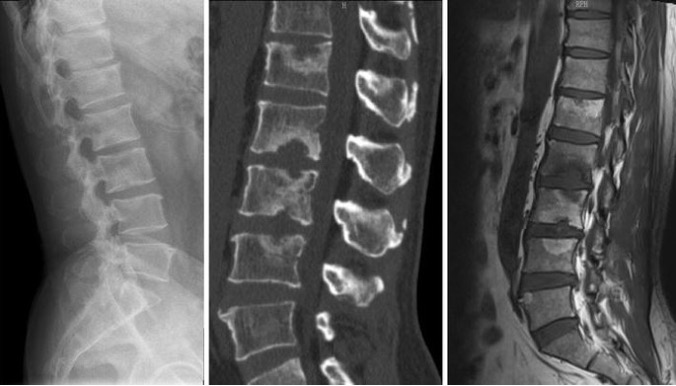

정의 : Scheuermann disease 는 성장기 청소년에서 척추 골단(end plate) 손상과 함께

척추체 앞쪽의 성장이 제한되어 후만증(kyphosis)이 발생하는 질환입니다.

진단 기준은 무엇일까?

Sorensen radiographic criteria 에서는 진단 기준을 이렇게 분류 하고 있습니다.

• 연속된 3개의 척추뼈에서 쐐기 변형이 5도 이상인 경우

• 척추의 골단(apophysis) 부위에서 불규칙한 선과 평탄화,쐐기형 변형

• 디스크 간격 좁아짐.

• Schmorl’s node가 존재할 수 있습니다.

Scheuermann disease는 주로 등뼈 에서 많이 발생하지만 요추에서도 발생할 수 있고

이러한 변화는 척추체의 앞쪽 성장을 막으면서 구조적 변화로 이어지고 endplate가 약해지면서 디스크 높이 감소 디스크 퇴행을 가속화 시켜 반복적인 통증과 신경증상이 나타날 수 있습니다. Scheuermann disease는 관리가 필요한 질환 입니다. 보존적 치료를 선택한다면 수면 , 스트레스 , 반복적인 부하 , 과한 운동의 관리가 필요합니다. 단순히 운동을 하는 것이 아닌 다차원적인 접근이 필요합니다.